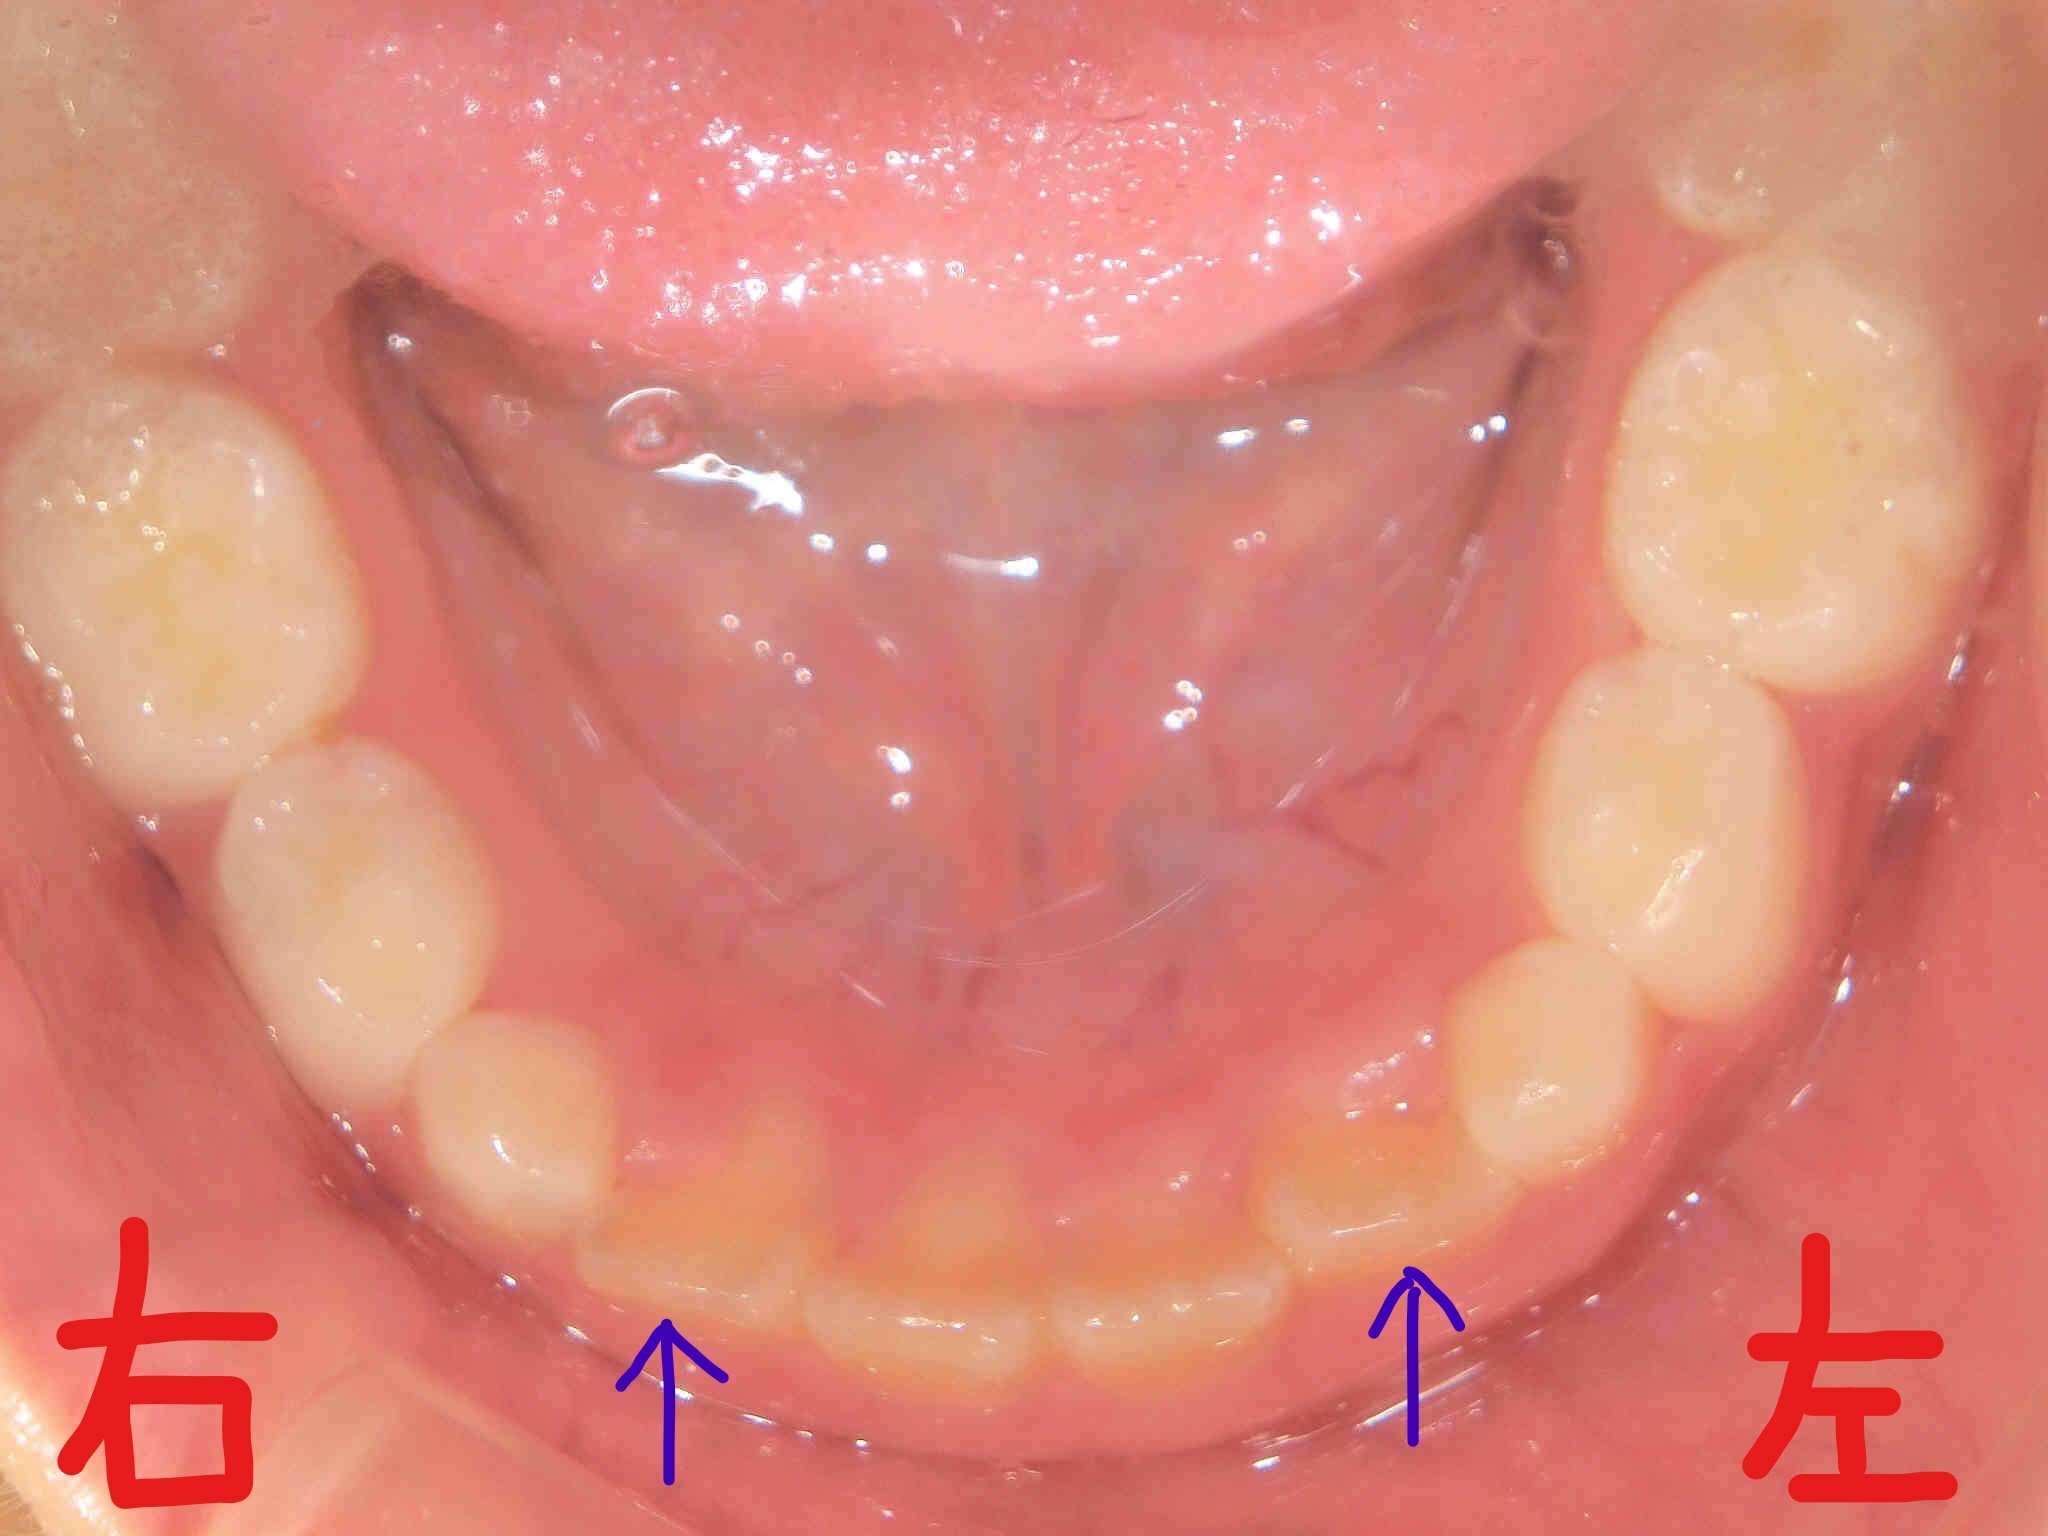

上記写真は、当時8歳の女児の、2017年2月時点における下顎の歯並びです。下顎前歯(青色矢印)がかなり内側に萌出している様子が確認できます。